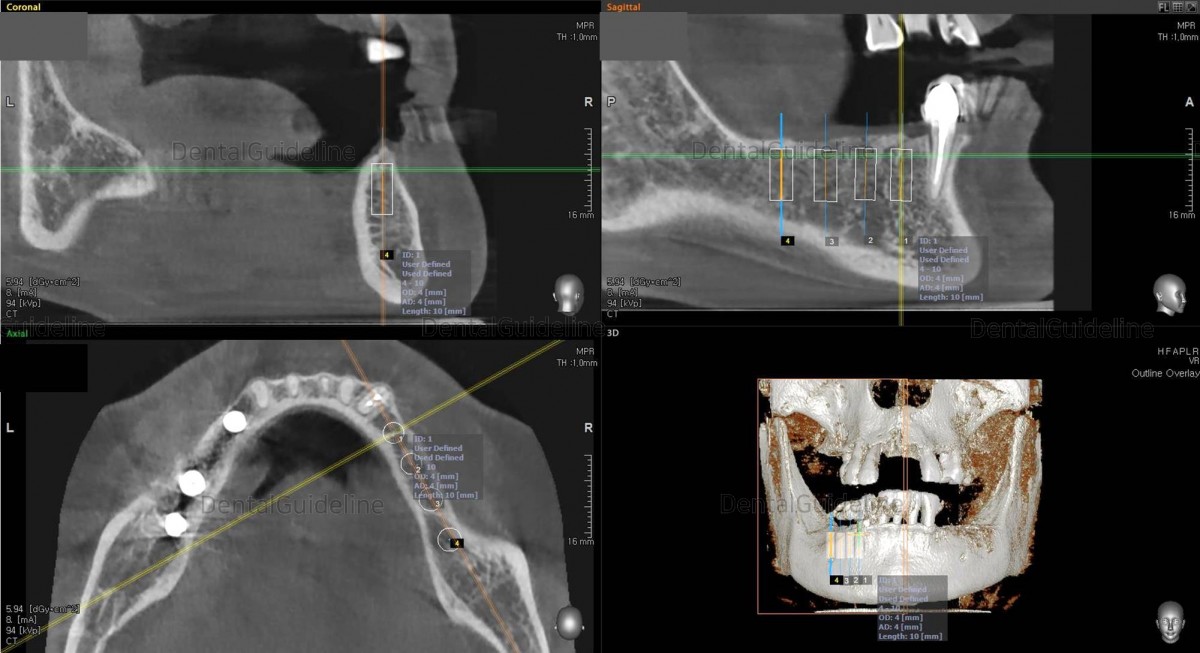

CBCT

scan. Arum NB-1 Ø4.0/L10

CBCT scan Arum NB-1 Ø4.5/ L10

(20Ncm) at

the 2nd molar zone.Arm Dentistry NB-1 Ø4.5/ L10